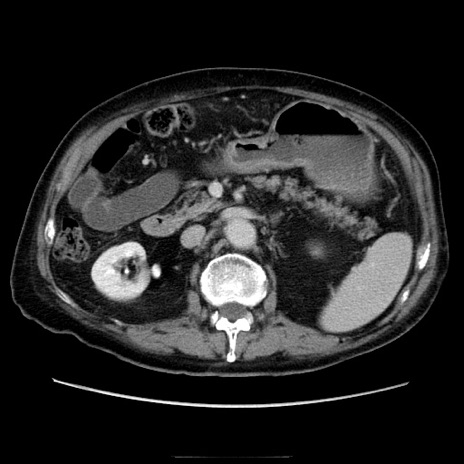

症例21(横断像)

【症例】70歳代男性

【主訴】腹痛

【現病歴】肝硬変・肝細胞癌にてかかりつけの方。約9時間前に食後より腹痛出現。症状が徐々に増悪し、嘔吐出現したため来院。

【既往歴】肝硬変、肝細胞癌(RFA、TACE後)

【身体所見】意識清明、表情苦悶様、BT 36℃、BP 129/78mmHg、P 88bpm、SpO2 97%(RA)、右上腹部から心窩部にかけて圧痛あり、反跳痛なし、筋性防御あり。

【データ】WBC 5800、CRP 0.16